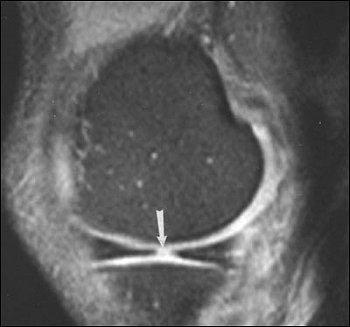

| Sixty-six-year-old man with radial tear of lateral meniscus. Above, axial fat-saturated fast spin-echo proton density-weighted image (TR/TE, 2,717/54; slice thickness, 4 mm) of right knee shows well-defined linear increased intensity (arrow) in body of lateral meniscus starting from free edge. Below, coronal fat-saturated fast spin-echo proton density-weighted image (3,750/60; slice thickness, 4 mm) shows tear as vertical defect in body of lateral meniscus (arrow). Tarhan NC, et al, "Meniscal Tears: Role of Axial MRI Alone and in Combination with Other Imaging Planes," (AJR 2004, Vol. 183, pp. 9-15). |